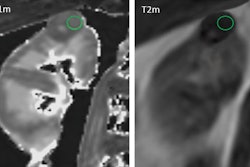

The AI functions by taking a preoperative CT scan as input, localizes the tumor region by segmenting it, and then predicts the probability of malignancy in a fully automated fashion, according to Aakanksha Rana, PhD, of Johnson & Johnson in New Brunswick, NJ.

Data from 289 histopathology-confirmed T1a patients were used to train and validate the deep learning-based pipeline that works in two phases: localizing the kidney and lesion regions (built on an nnUnet model), and classifying benign and malignant (built on a 3D Mobilnet model). Manual segmentations served as ground truth.

For classifying the lesions, the AI achieved an AUC of 0.87 and an accuracy of 0.82. For identifying benign, the AI showed a sensitivity of 0.89 and a specificity of 0.81. Validation metrics also included dice which achieved "a remarkable segmentation" dice score of 0.83 for precise localization, according to Rana.

This work emphasizes that there is an opportunity to reduce the diagnostic challenges of T1a RCCs considering their prevalence. The end-to-end "localize to classify" cascade of convolutional neural networks (CNNs) used to segment the tumor for precise localization was effective at differentiating T1a renal masses as benign or malignant. However, more work is needed to validate the tool on a larger dataset taking into account other factors.